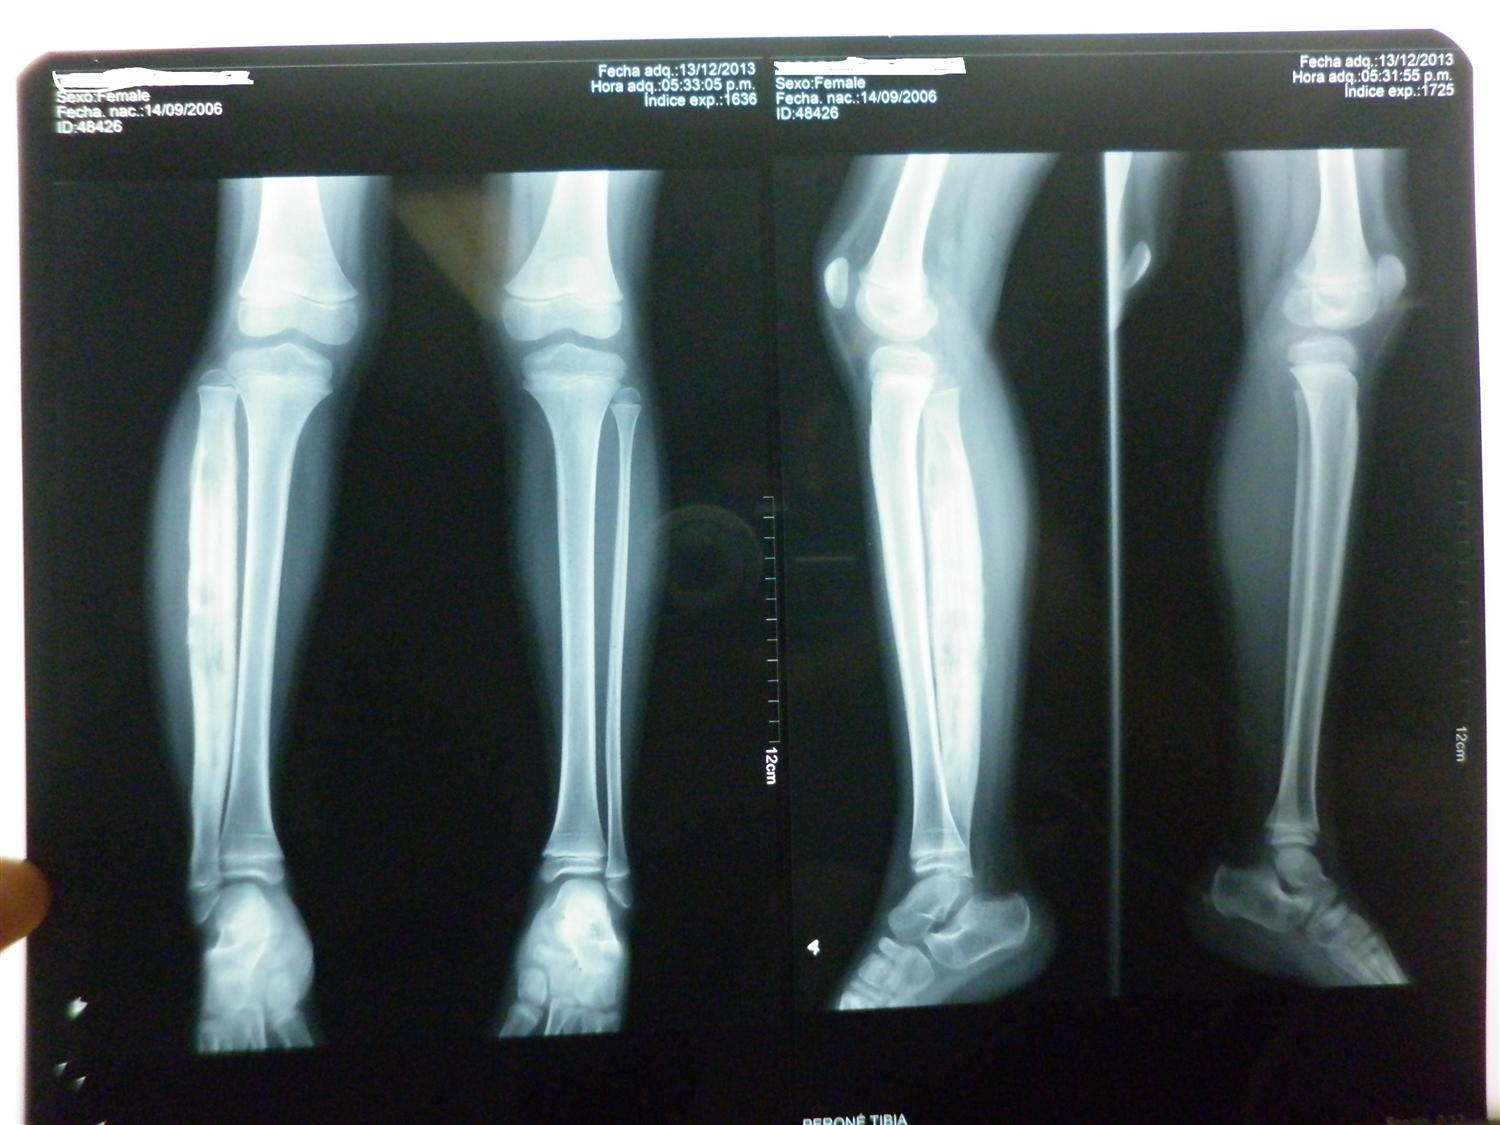

Radiology case Osteomyelitis of toe

Case 3 Osteomyelitis of the lower leg. (a) Preoperativ Openi What Is Osteomyelitis Of The Foot Symptoms include pain and tenderness over the affected area of bone,. It usually goes away if treated early with antibiotics. osteomyelitis is an infection and inflammation of the bone. osteomyelitis is a painful bone infection. osteomyelitis (bone infection) osteomyelitis is a serious infection that happens when bacteria or fungi infect your. osteomyelitis is an inflammation or. What Is Osteomyelitis Of The Foot.